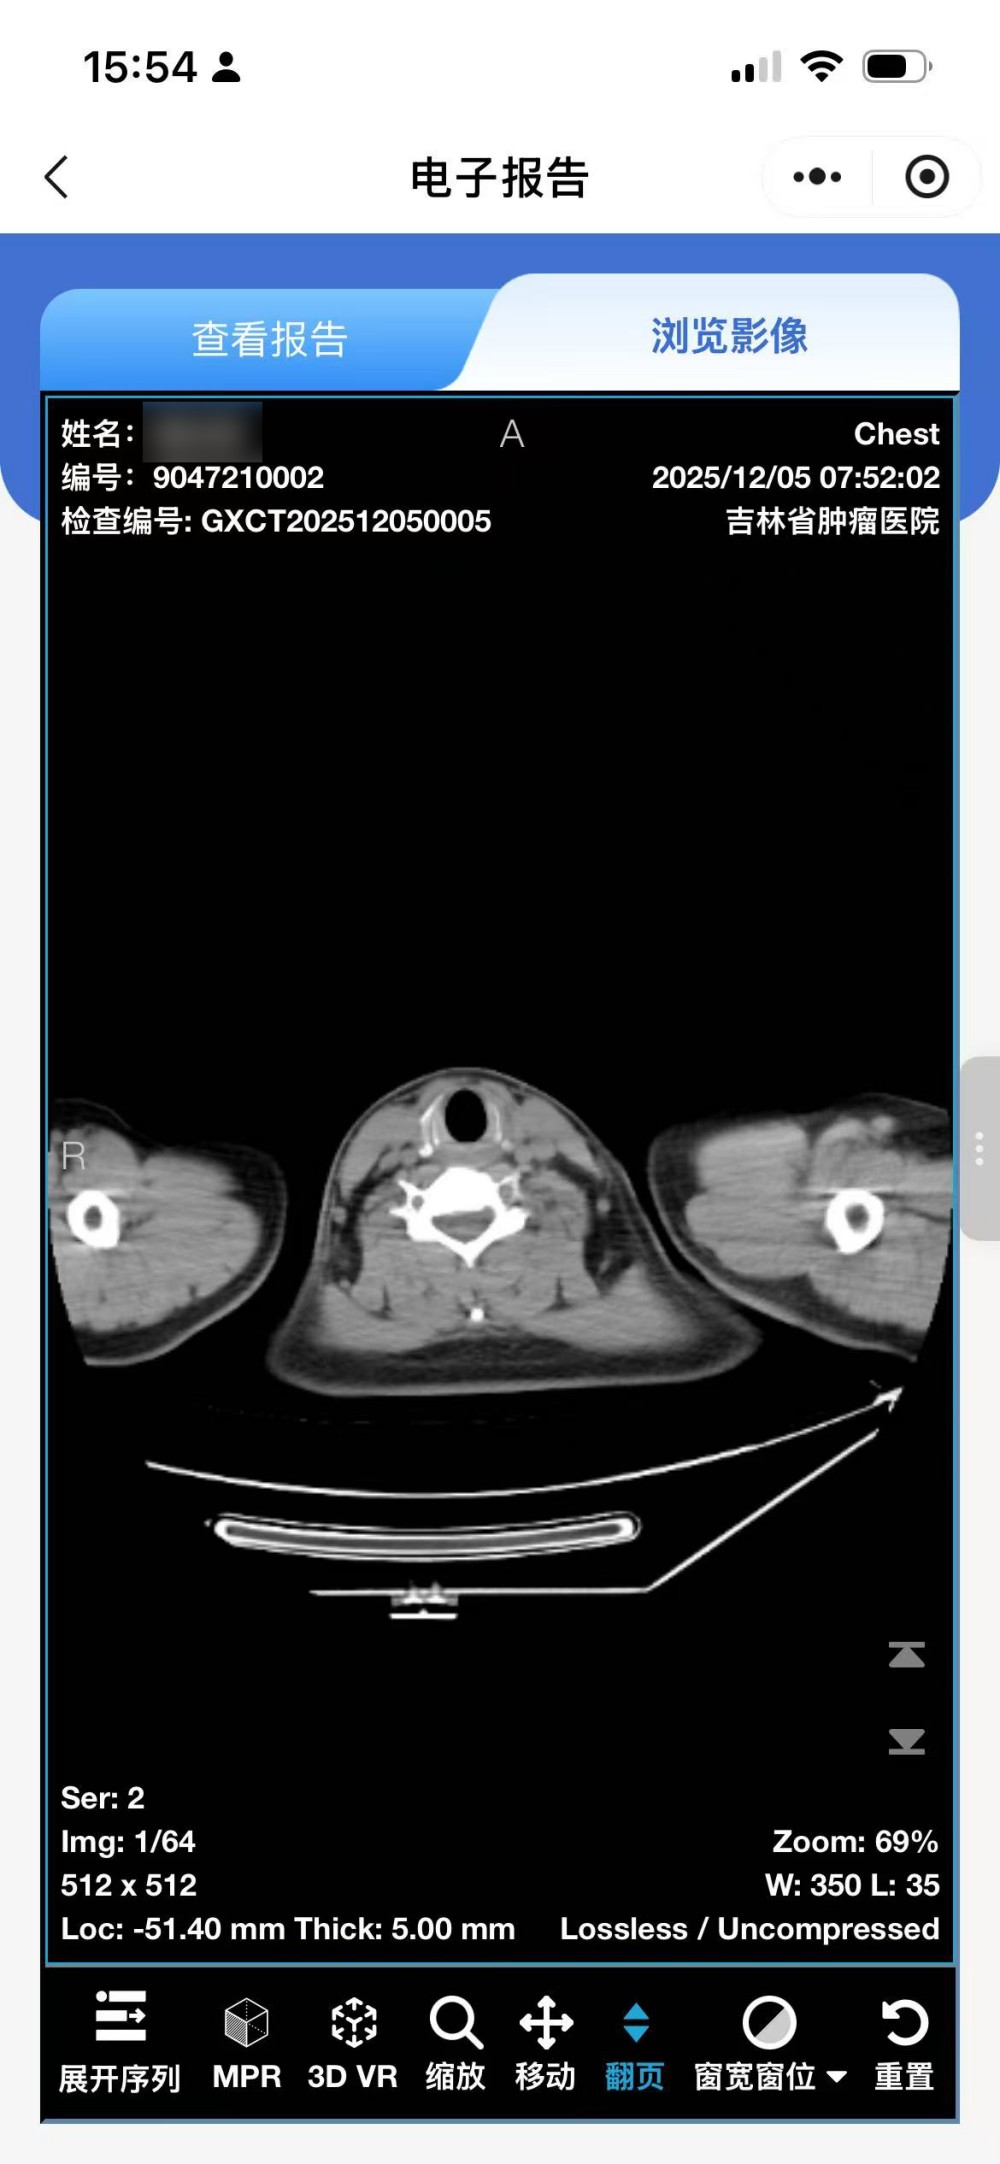

• 点击查看报告:阅读检查所见、检查印象等完整文字报告

• 点击浏览影像:查看全套影像序列,可逐张浏览具体影像图